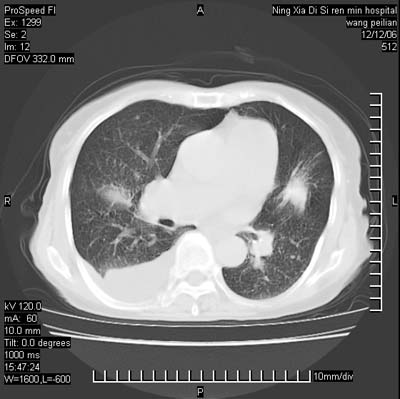

标题: CT5609:胸部:女77 病史不详 [打印本页]

标题: CT5609:胸部:女77 病史不详

两肺可见多个大小不等的结节,左侧有胸水,纵隔淋巴结增大,考虑是细支气管肺泡癌

两肺尖纤维索状影,两下肺结节块状影,且有钙化灶,右胸腔积液。考虑肺结核并胸膜炎。

双侧肺结核伴右侧胸腔积液.

两肺尖纤维索状影,两下肺结节块状影,且有钙化灶,右胸腔积液。考虑肺结核并胸膜炎肺间质纤维化

考虑:1、慢性支气管炎合并全小叶型肺气肿、间质纤维化;

2、双肺结核;

3、右侧胸膜炎(积液)。

1、双肺继发型肺结核(以纤维、增殖灶为主);

2、右侧胸腔积液;

3、其余符合老年肺改变。

双肺见多个结节状及条索状影,双侧胸腔积液,右侧叶间积液,考虑结核性胸膜炎